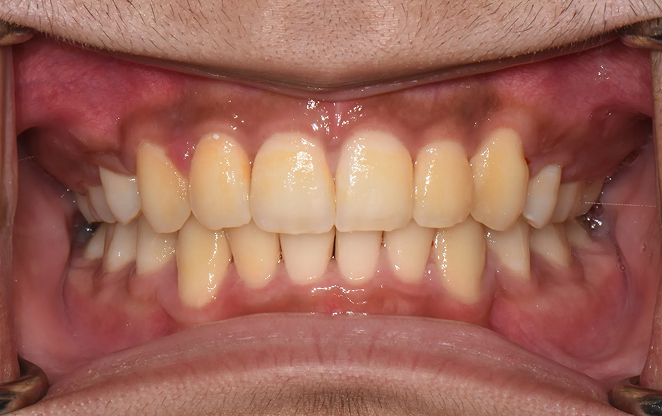

Before

After